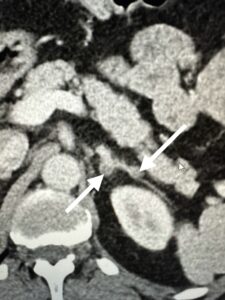

CT of the adrenal glands demonstrated bilateral adrenal nodules. The largest nodule measured 1.9 cm.